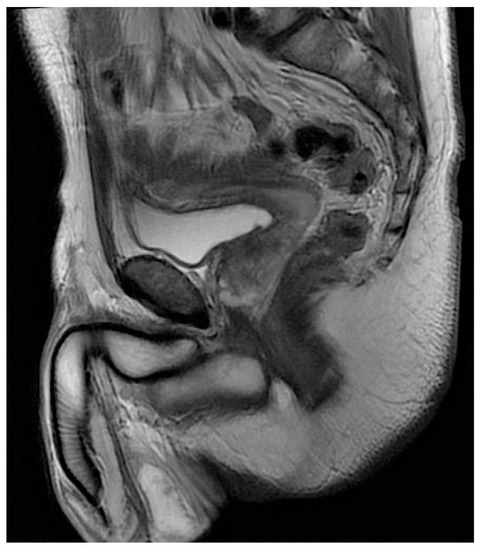

3. Case Report